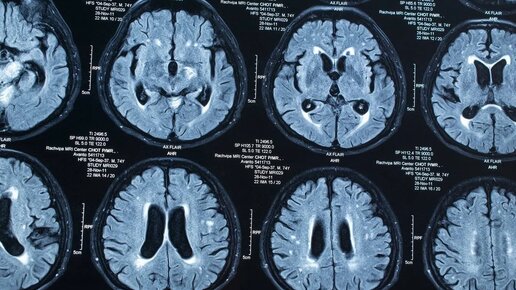

Головной и спинной мозг окружены специфической по составу и свойствам жидкостью, которую называют спинномозговой (цереброспинальной) жидкостью или ликвором. Свежая спинномозговая жидкость непрерывно производится мозгом каждый день. Он циркулирует вокруг головного и спинного мозга, перенося питательные вещества, смывая загрязнения, отводя продукты метаболизма и смягчая сотрясения, удары в области этих деликатных структур. Спинномозговая жидкость течет через систему желудочков внутри головного мозга,...